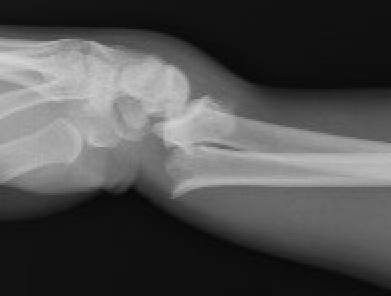

| Colle's fracture | Smith's fracture | Chauffeur's Fracture |

| Distal radius fracture with dorsal displacement | Distal radius fracture with volar displacement | Radial styloid fracture |